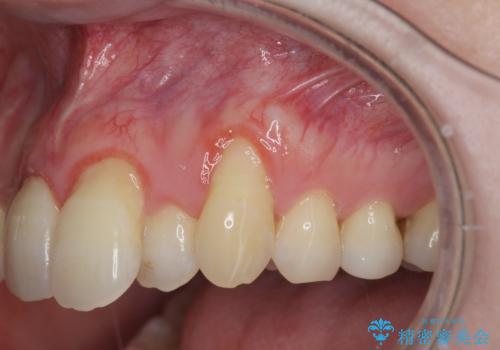

目立つ八重歯の歯ぐきのさがり 根面被覆による改善

- 長年気になっていた歯ぐきのさがり(歯肉退縮)の相談で来院されました。

ブラッシング指導をまず行い、硬すぎる歯ブラシを使用しないこと、歯ブラシの当て方を確認しました。

プラークコントロールが十分に行えるようになったのち、結合組織移植を用いた根面被覆手術を行います。